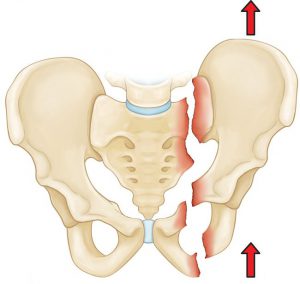

The Cost of Hip Fracture Surgery, Hip fractures are common injuries, especially among the elderly and individuals with osteoporosis. Patients often seek the best surgeon to help them resolve this issue and alleviate the pain they are experiencing. In the following paragraphs, we will shed light on hip fractures, their causes, symptoms, the surgical procedure, and the resulting outcomes. Stay with us to learn more.

As mentioned earlier, hip fracture is a serious injury that occurs when the hip bones are broken. This type of injury often requires immediate medical attention, and the symptoms that may appear in the case of a hip fracture include:

Causes of Hip Fracture

There are some reasons that lead to hip fractures, including:

- Falling from a high place.

- Exposure to strong accidents and injuries.

- People with osteoporosis are more susceptible to fractures from simple movements or falling to the ground.

- Continuous pressure on the hip bones, such as during strenuous physical exercise.

Hip fracture surgery is performed to realign the broken bones to their proper position before the fracture occurred. This is done through one of the following methods:

- Open Reduction: In this procedure, a surgical incision is made in the hip skin, allowing the surgeon to directly manipulate the bones’ alignment.

- Closed Reduction: In this approach, the doctor modifies the bones’ position without making a surgical incision. The procedure typically lasts about two to three hours, and in some complex cases, it may require more time. The patient is put under general anesthesia and may spend a few hours in the recovery room after the operation.

Whether the doctor chooses an open reduction or closed reduction, they will work to stabilize the bones to prevent them from moving during the healing period. This is achieved using internal or external fixation with specific medical devices such as wires, pins, screws, or plates. These devices are usually removed after 6 to 12 months following the surgery.